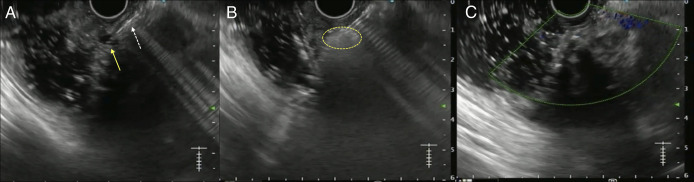

Expanding Horizons of Vascular Interventions: Endoscopic Ultrasound-Guided Angioembolization for a Refractory Upper Gastrointestinal Bleed From a Gastric Dieulafoy Lesion.